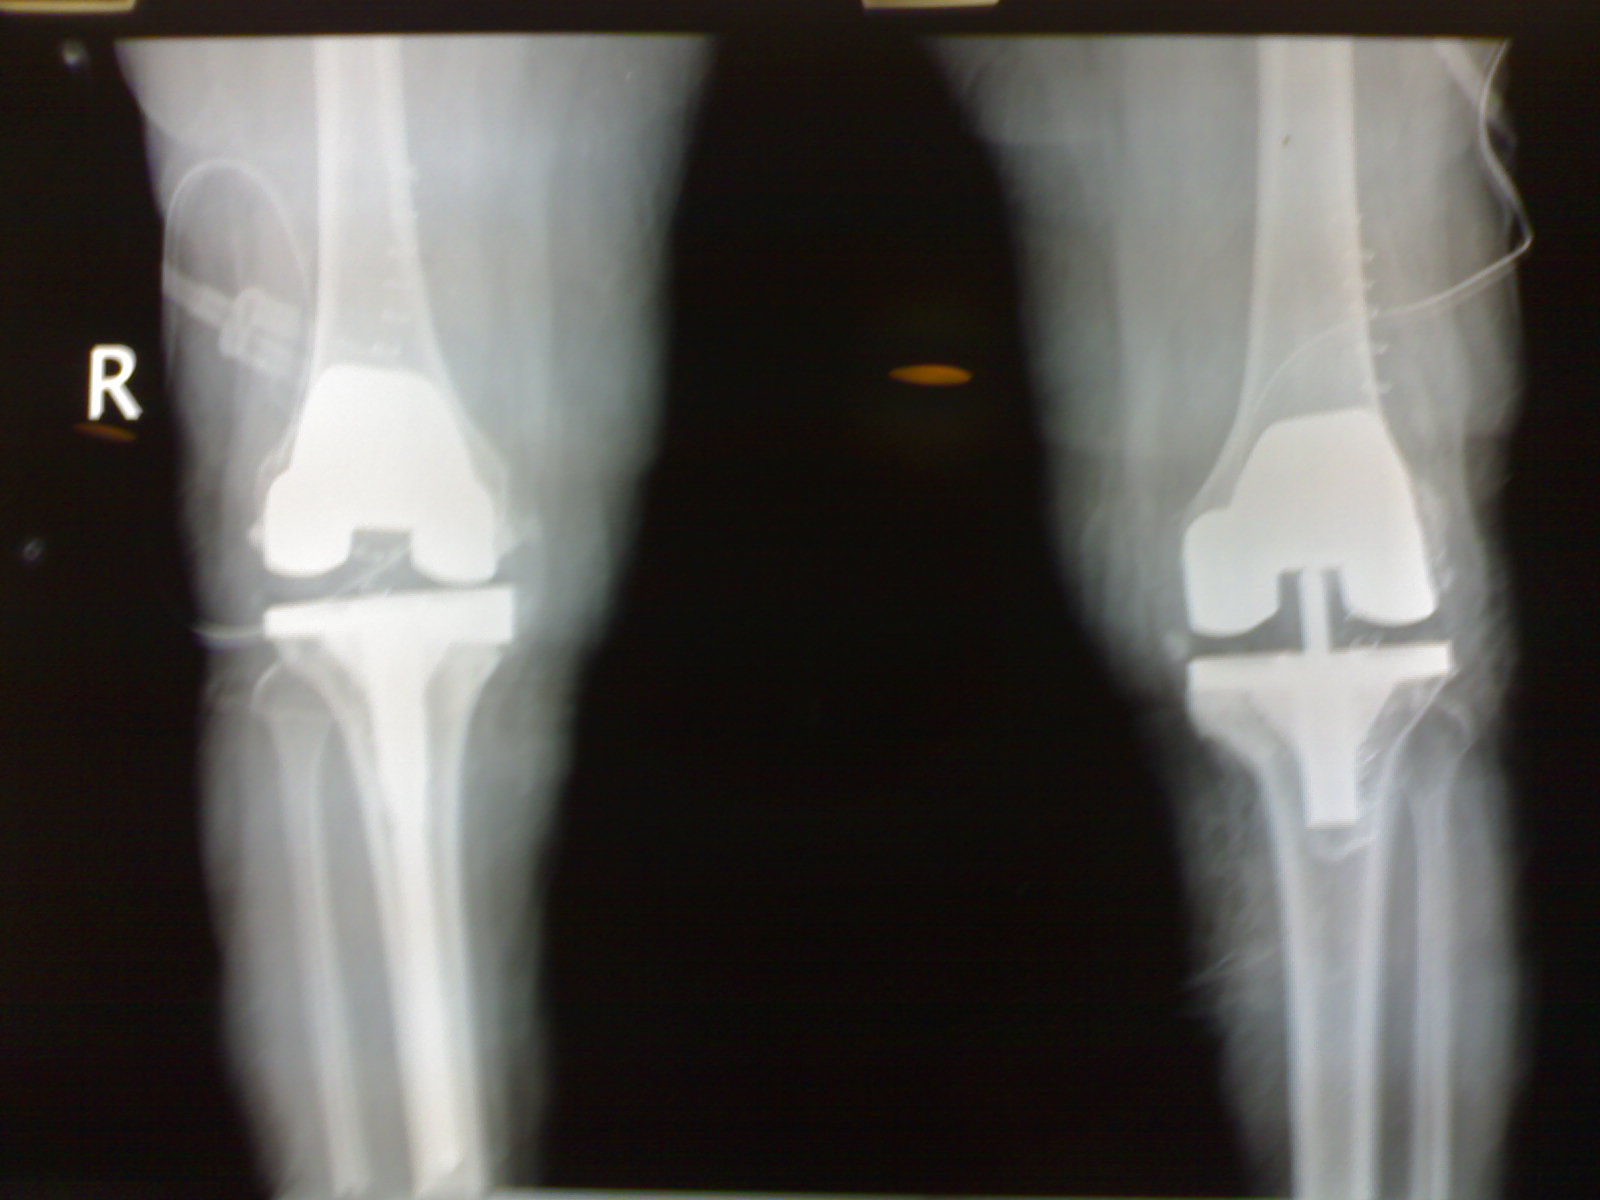

Procedure Just prior to the surgery relevant investigations were done. The patient underwent bilateral total knee replacement PFC with external tibial rods and step wedge. ... Access Document